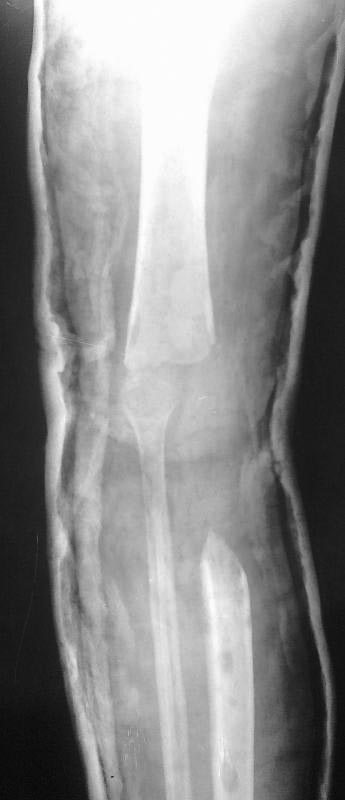

Пациентка 1972 года рождения. В сентябре 2012 года выполнена резекция дистального отдела бедра и проксимального отдела большеберцовой кости. В январе 2012 года оскольчатый внутрисуставной перелом проксимального отдела большеберцовой кости. был выполнен накостный синтез пластиной. Сопутствующая патология ВИЧ. Послеоперационный период осложнился нагноением раны и последующим остеомиелитом большеберцовой кости.Больная неоднократно оперировалась: удаление пластины,фиксация в аппарате, остеонекрэктомии. Из-за недостатка опыта не выполнили в свое время мышечную пластику с закрытием раны, в результате инфекция прогрессировала, распространилась на коленный сустав. В сентябре 2012 выполнена остеонекрэктомия (резекция мыщелков бедра, проксимальной 3 большеберцовой кости), рану закрыли, конечность фиксировали простым АВФ и лангетой. На данный момент имеет место укорочение конечности до 10 см, отека,гиперемии,ран,свищей нет, чувствительность и движения в стопе сохранены, пульс на артериях стопы хороший. Имеет место анемия (87), аппарат снят, конечность фиксирована лангетой, больна уверенно передвигается на костылях. Планируется восстановить опорную конечность используя проксимальный отдел малоберцовой кости для замещения дефекта закрыто в АВФ (что-то вроде операции Гана), возможно с удлинением конечности.Хотелось бы узнать Ваше мнение о тактике лечения данной пациентки.